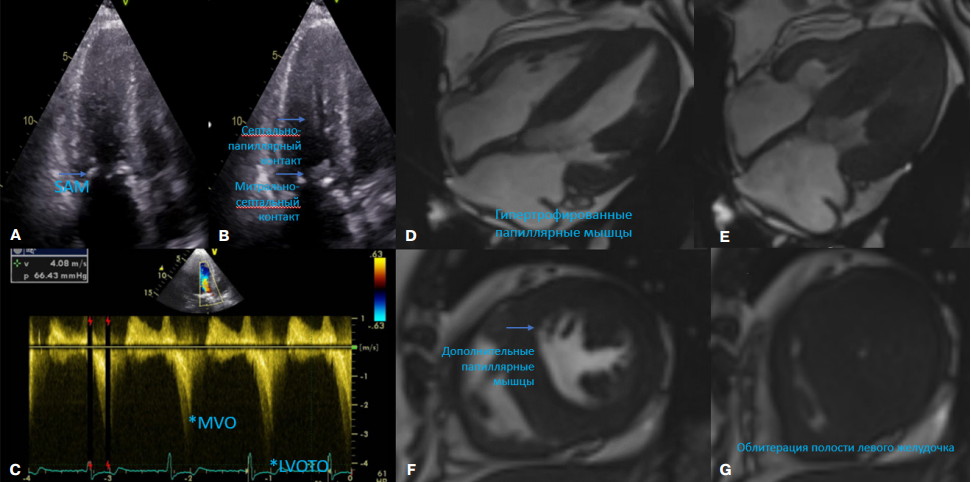

- Болезнь Фабри (БФ) с преимущественным поражением сердца может имитировать гипертрофическую кардиомиопатию и сопровождаться обструкцией выносящего тракта и даже средне-желудочковой обструкцией.

Введение. Болезнь Фабри (БФ) может имитировать гипертрофическую кардиомиопатию и сопровождаться обструкцией выносящего тракта левого желудочка или средне-желудочковой обструкцией. В случае наличия у пациента внутриполостной обструкции и рефрактерной к медикаментозной терапии сердечной недостаточности может быть рассмотрена септальная редукция.

Краткое описание. Нами представлен случай этаноловой септальной аблации (ЭСА) у пациента женского пола с генетически подтвержденной БФ и симптоматической многоуровневой внутриполостной обструкцией. Ей проведена транскатетерная ЭСА с последующим устранением средне-желудочковой обструкции и обструкции выносящего тракта левого желудочка. Гемодинамический эффект сохранялся в течение последующих 3 мес. наблюдения.

Дискуссия. Наш случай иллюстрирует факт, что ЭСА может быть эффективной и безопасной в устранении обструкции у пациентов с БФ при условии дальнейшего наблюдения за внутрисердечной гемодинамикой.